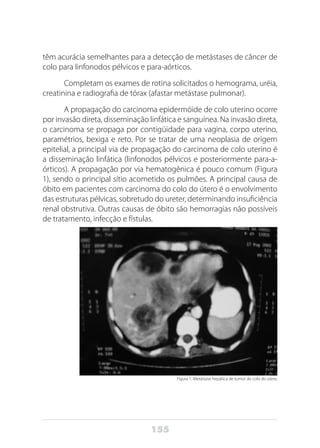

o tumor se desenvolve. O tumor que se localiza na cabeça do pâncreas

apresenta como sintoma comum a icterícia acompanhada de prurido e

que é decorrente da compressão extrínseca do ducto biliar. A compres-